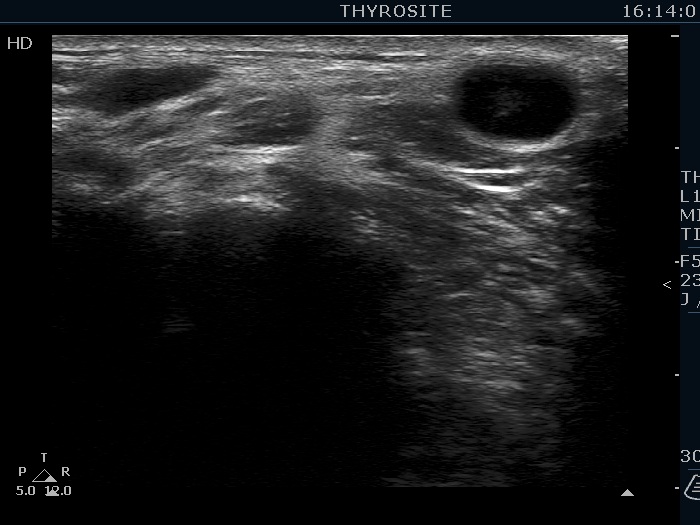

Ultrasonography. The thyroid was echonormal. There were several hypoechoic nodules in the left lobe. The middle one had back wall cystic figures. There were 3 or four discrete, deeply hypoechoic lesions above and lateral to the left lobe in the neck. One of them presented with a hilum-like figure while the others lacked hilum.

Aspiration cytology of the lesion in the middle part of the left lobe resulted in benign lesion. One of the masses in the neck was also aspirated and a heterogeneous lymphoid cell population was gained. Wash-out thyroglobulin resulted in 13 ng/mL, while serum thyroglobulin was 19.4 ng/mL.

The lymph nodes had a non-typical presentation. They lacked a regular hilum.